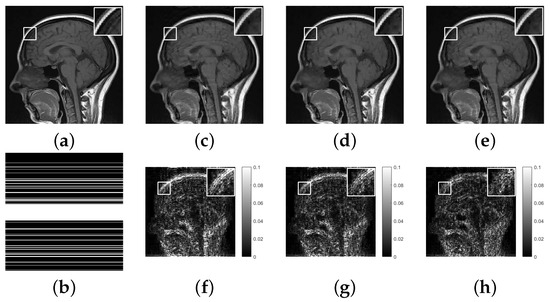

Figure 2. (a), Original image; (b), undersampling template with 30 % sampling rate; (ce), reconstructed images using 1 regularization, 1 / 2 regularization and GMC regularization, respectively; (f), difference between (a) and (c); (g), difference between (a) and (d); (h), difference between (a) and (e).

To further enhance the visual contrast effect, we calculated the difference between the reconstructed image and the original image. Furthermore, we magnified a small portion of the local image to show more details. The reconstruction results of three regularizations are shown in Figure 2, Figure 3 and Figure 4. It can be found that the reconstructed images based on 1 regularization have problems such as blurred edges and residual shadows, and the 1 / 2 regularization reconstruction model also shows similar phenomena. In contrast, the reconstructed images based on GMC sparse regularization are closer to the original images and exhibit higher reconstruction quality.

Additionally, we conducted a quantitative evaluation of the reconstruction results in Table 1. It is obvious that compared with 1 and 1 / 2 regularization, GMC sparse regularization has the best performance in MRI reconstruction and can obtain the lowest RE and highest PSNR.